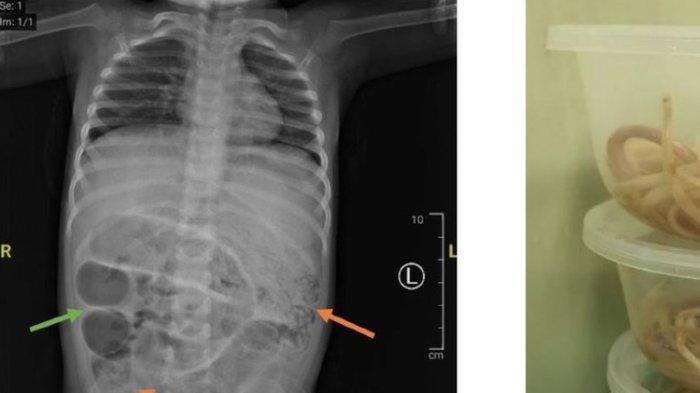

Viral perut anak usia 3 tahun dari Kabupaten Jember, Jawa Timur dipenuhi cacing, sehingga tidak bisa buang air besar (BAB).

TRIBUNJATENG.COM, JEMBER – Seorang balita harus menahan sakit di perutnya lantaran ada cacing yang menyumbat usus.

Bocah warga Jember Jawa Timur tersebut pun terpaksa menjalani operasi.

Hasilnya, didapati ada tiga titik sumbatan pada usus bocah usia tiga tahun tersebut.

Perut anak usia 3 tahun dari Kabupaten Jember, Jawa Timur dipenuhi cacing, sehingga tidak bisa buang air besar (BAB).

Cacing tersebut menumpuk di dalam usus anak tersebut, sehingga menyebabkan ususnya tidak berfungsi maksimal.

Akibatnya, selain tidak bisa BAB, juga mengalami sakit perut, sesak napas, hingga muntah.

Anak tersebut dibawa ke RSD dr Soebandi Jember dan dioperasi oleh empat dokter.

Hasil tindakan operasi, ditemukan gumpalan cacing di dalam ususnya.

“Cacingnya seperti cacing tanah, cacing ascariasis namanya, bukan cacing pita,” kata Direktur RSD dr Soebandi Jember, Dr dr I Nyoman Semita seperti dilansir dari Kompas.com, Minggu (13/4/2025).